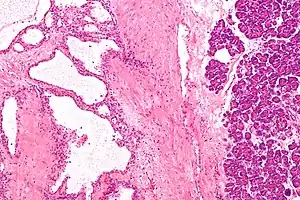

| Micrograph showing a pancreatic serous cystadenoma. H&E stain. | |